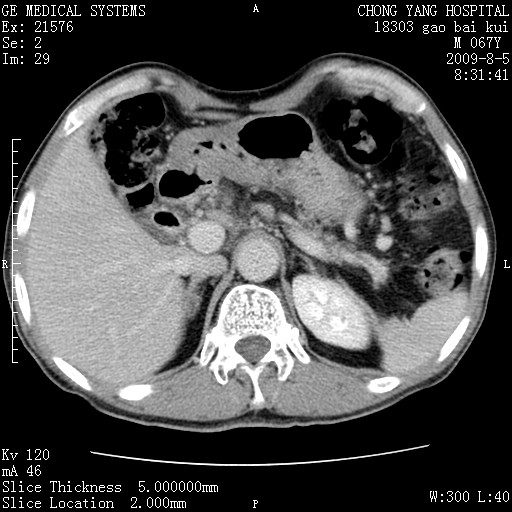

这个也过了,考虑胰腺钩突癌或壶腹癌,不除外胰管粘液乳头瘤伴胰管扩张,肝内胆管积气.

1)考虑胰头癌或壶腹癌并胰管扩张。2)肝外胆管扩张、积气,胆囊影未见;考虑术后改变。3)胃壁增厚?建议必要时行胃镜检查。

虑胰腺钩突癌或壶腹癌,不除外胰管粘液乳头瘤伴胰管扩张,肝内胆管积气.

考虑胰头癌并十二指肠受侵。